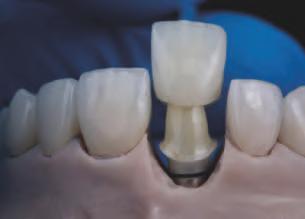

Un ob ect v pr nc pal al restaurăr lor dentare este să m te d nț natural în armon e cu fața nd v dulu . S-a demonstrat de mult t mp că un zâmbet atrăgător are un mpact semn f cat v asupra percepț e ș a d scernământulu celorlalț . De-a lungul an lor, în stomatolog a estet că s-au făcut progrese substanț ale, în spec al în ceea ce pr vește avansarea tehnolog lor d g tale care fac l tează pro ectarea

tr d mens onală (3D) a zâmbetulu , personal zată, în armon e cu fața pac entulu . Deoarece percepț a estet c dentofac ale este determnată ș de prefer nțele personale ș de factor cultural , este esenț ală ntegrarea pac entulu în procesul dec z onal pentru a at nge ob ectvele opt me de tratament estet c. În ult mele decen , pro ectarea zâmbetulu s-a mutat progres v de la fluxur de lucru analog ce la d g ta-

le, care s-au dezvoltat ulter or de la nstrumentele b d mens onale (2D) la cele tr d mens onale (3D). Implementarea nstrumentelor d g tale ș a nteracț un onl ne a îmbunătăț t comun carea între cl n c en , tehnc en dentar ș pac enț . Îmb narea fotograf lor 2D cu f ș erele d g tale 3D perm te tranz ț a către un flux de lucru complet d g tal ș fac l tează pro ectarea d g tală a zâmbetulu gh dată fac al. Instrumentele no de

pro ectare d g tală a zâmbetulu pot f folos te pentru a contura ș mod f ca d g tal zâmbetele pac enț lor dar ș pentru a v zual za rezultatul îna nte de pract carea unor procedur revers b le. De asemenea, astfel de nstrumente perm t anal za met culoasă a caracter st c lor fac ale ș dentare ale pac entulu pentru a fac l ta pro ectarea d g tală. În mod ob șnu t, un f ș er STL al pro ectăr d g tale a zâmbetulu este mpr mat în 3D, ar acest model este folos t pentru producerea une s mulăr în scaunul stomatolog c. Ver f carea tuturor parametr lor estet c este esenț ală, deoarece aceeaș pro ectare 3D a zâmbetulu sau o mod f care corespunzătoare a aceste a este ut l zată pentru fabr carea restaurăr lor def n t ve. De fapt, toț paș ulter or , nclus v t pul de tratament restaurator, mater alul ș pro ectarea preparaț e dep nd d rect de prec z a aceste pro ectăr n ț ale.